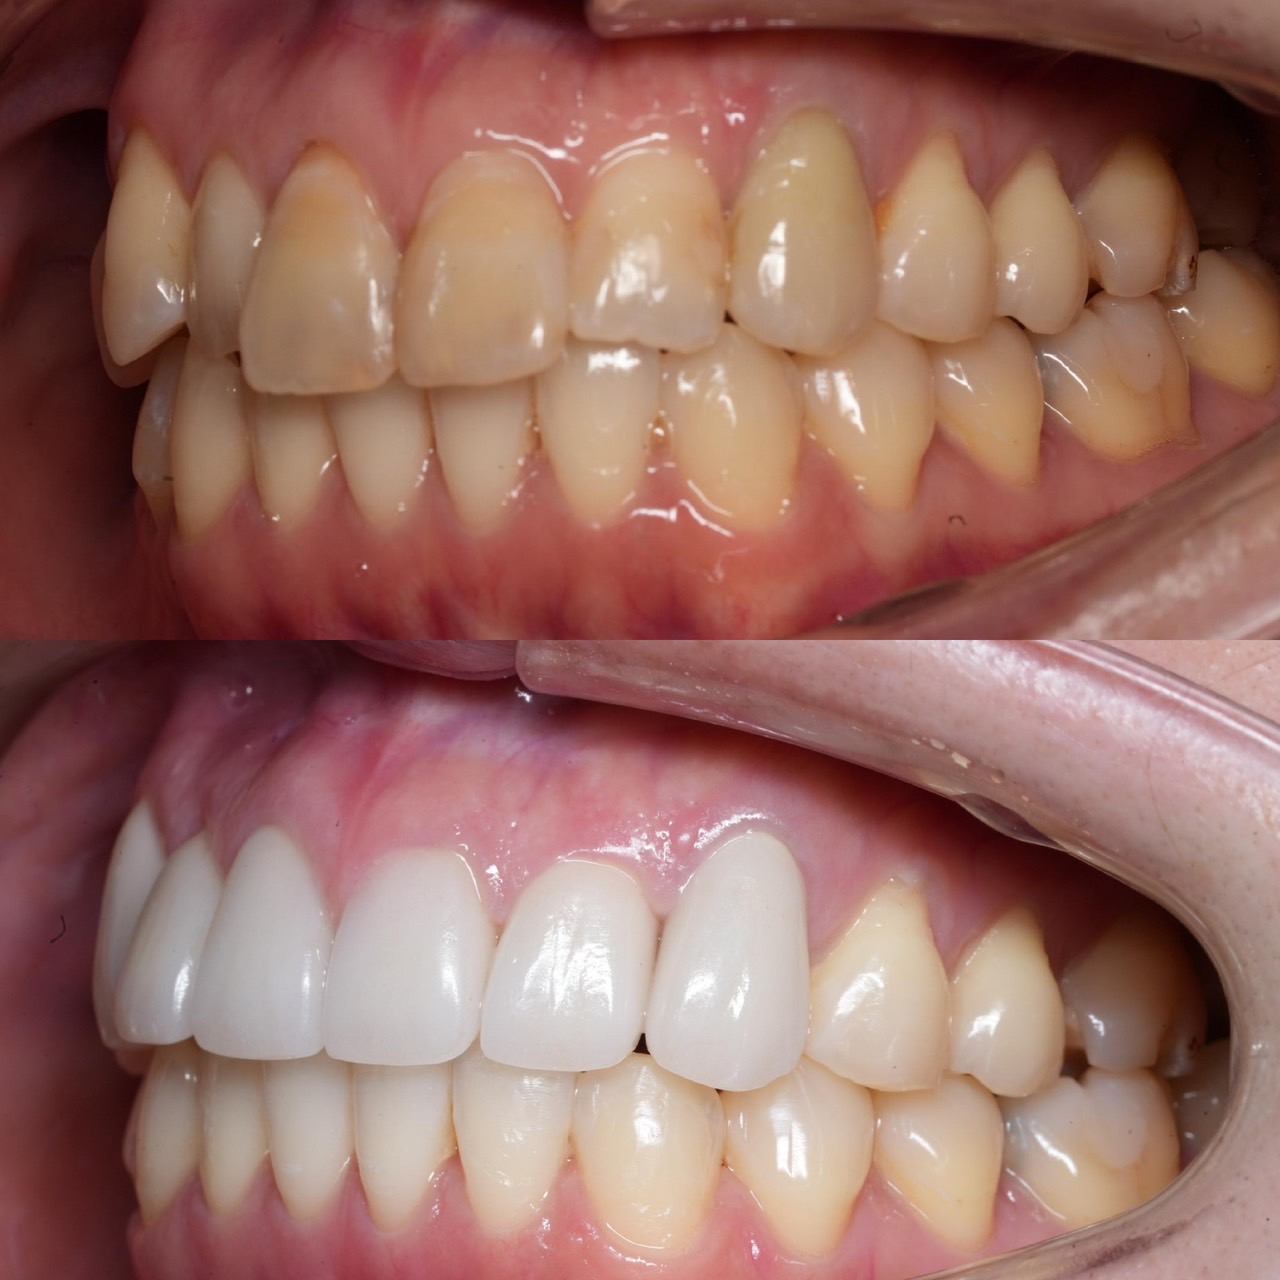

Case031

前歯が虫歯なのと、保険のプラスチックで大きく治療されていて色が悪いこと、歯並びが出っ歯気味であることを気にしてセラミックにしたいという主訴で来院された患者様です。

初診時を含めてトータル4回のご来院で完了です。

今回は前歯を下げる、歯列を整える、白すぎず自然に綺麗に見える色というご希望に沿って治療しました。